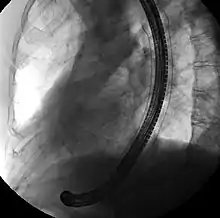

Esophageal SEMS are placed after a gastroscopy is performed to identify the area of narrowing. The area may need to be dilated to allow the gastroscope to pass.[14] The tumour is usually better seen with the direct vision of endoscopy than on a fluoroscopic image. As a result, radio-opaque markers are usually placed on the surface of the patient to mark the area of narrowing on fluoroscopy. The SEMS is placed through the channel of the endoscope into the esophagus over a guidewire, marked on fluoroscopy, and mechanically deployed (using a device that sits outside of the endoscope) such that it expands when in position. Hypaque or other water-soluble dye may be placed through the passage to ensure patency of the stent on fluoroscopy.[15] Enteric and colonic SEMS are inserted in a similar fashion, but in the duodenum and colon respectively.[16]

Biliary SEMS are used to palliatively treat tumours of the pancreas or bile duct that obstruct the common bile duct. They are inserted at the time of ERCP, a procedure that uses endoscopy and fluoroscopy to access the common bile duct. The bile duct is cannulated with the assistance of a guidewire and the sphincter of Oddi that is located at its base is typically cut. A wire is kept in the bile duct, and the SEMS is deployed over the wire in a similar fashion as esophageal stents. The location of the SEMS is confirmed by fluoroscopy.[17]